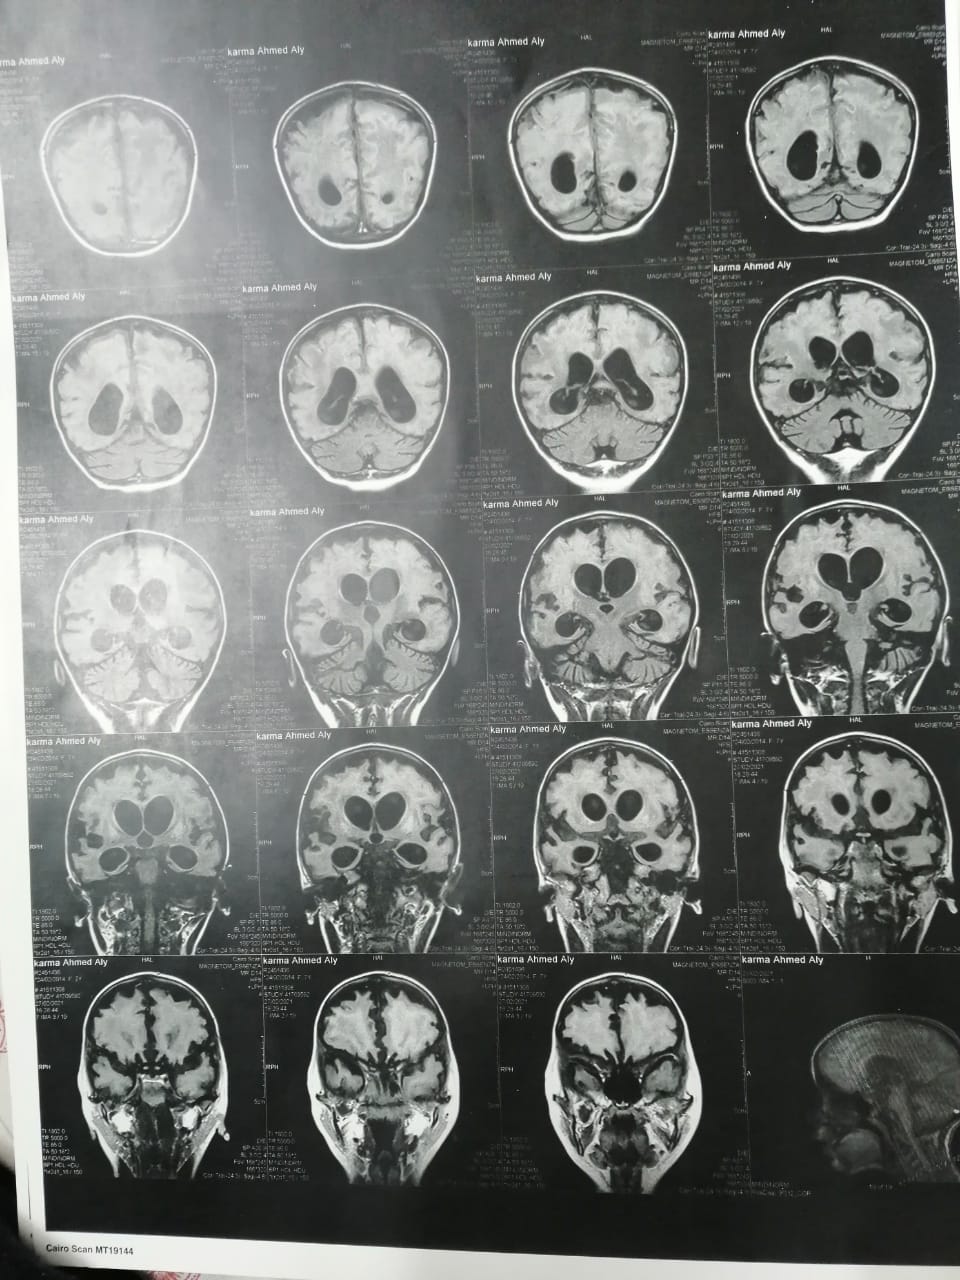

وأشار إلى أنه بعد خروج كارما من المستشفى تم إجراء فحوصات أخرى عليها، تبينت عدم التطابق بين التقارير الطبية لها بداخل المستشفى والفحوصات الجديدة.

وقال علي: "بنتي جالها ضمور في المخ وفي كل الحواس، بسبب الدوا الغلط، بنعملها علاج طبيعي بيتكلف في الشهر 20 ألف جنيه"، مشددًا": "هي بتفتح عينها بس".

وأكد تواصله مع مستشفى بألمانيا وعرض عليهم حالة ابنته وبالفعل تم قبولها، مشيرًا: "التكلفة عالية جدًا عاوزين 92 ألف يورو، أنا مقدرش عليها، وده علاجها الوحيد".